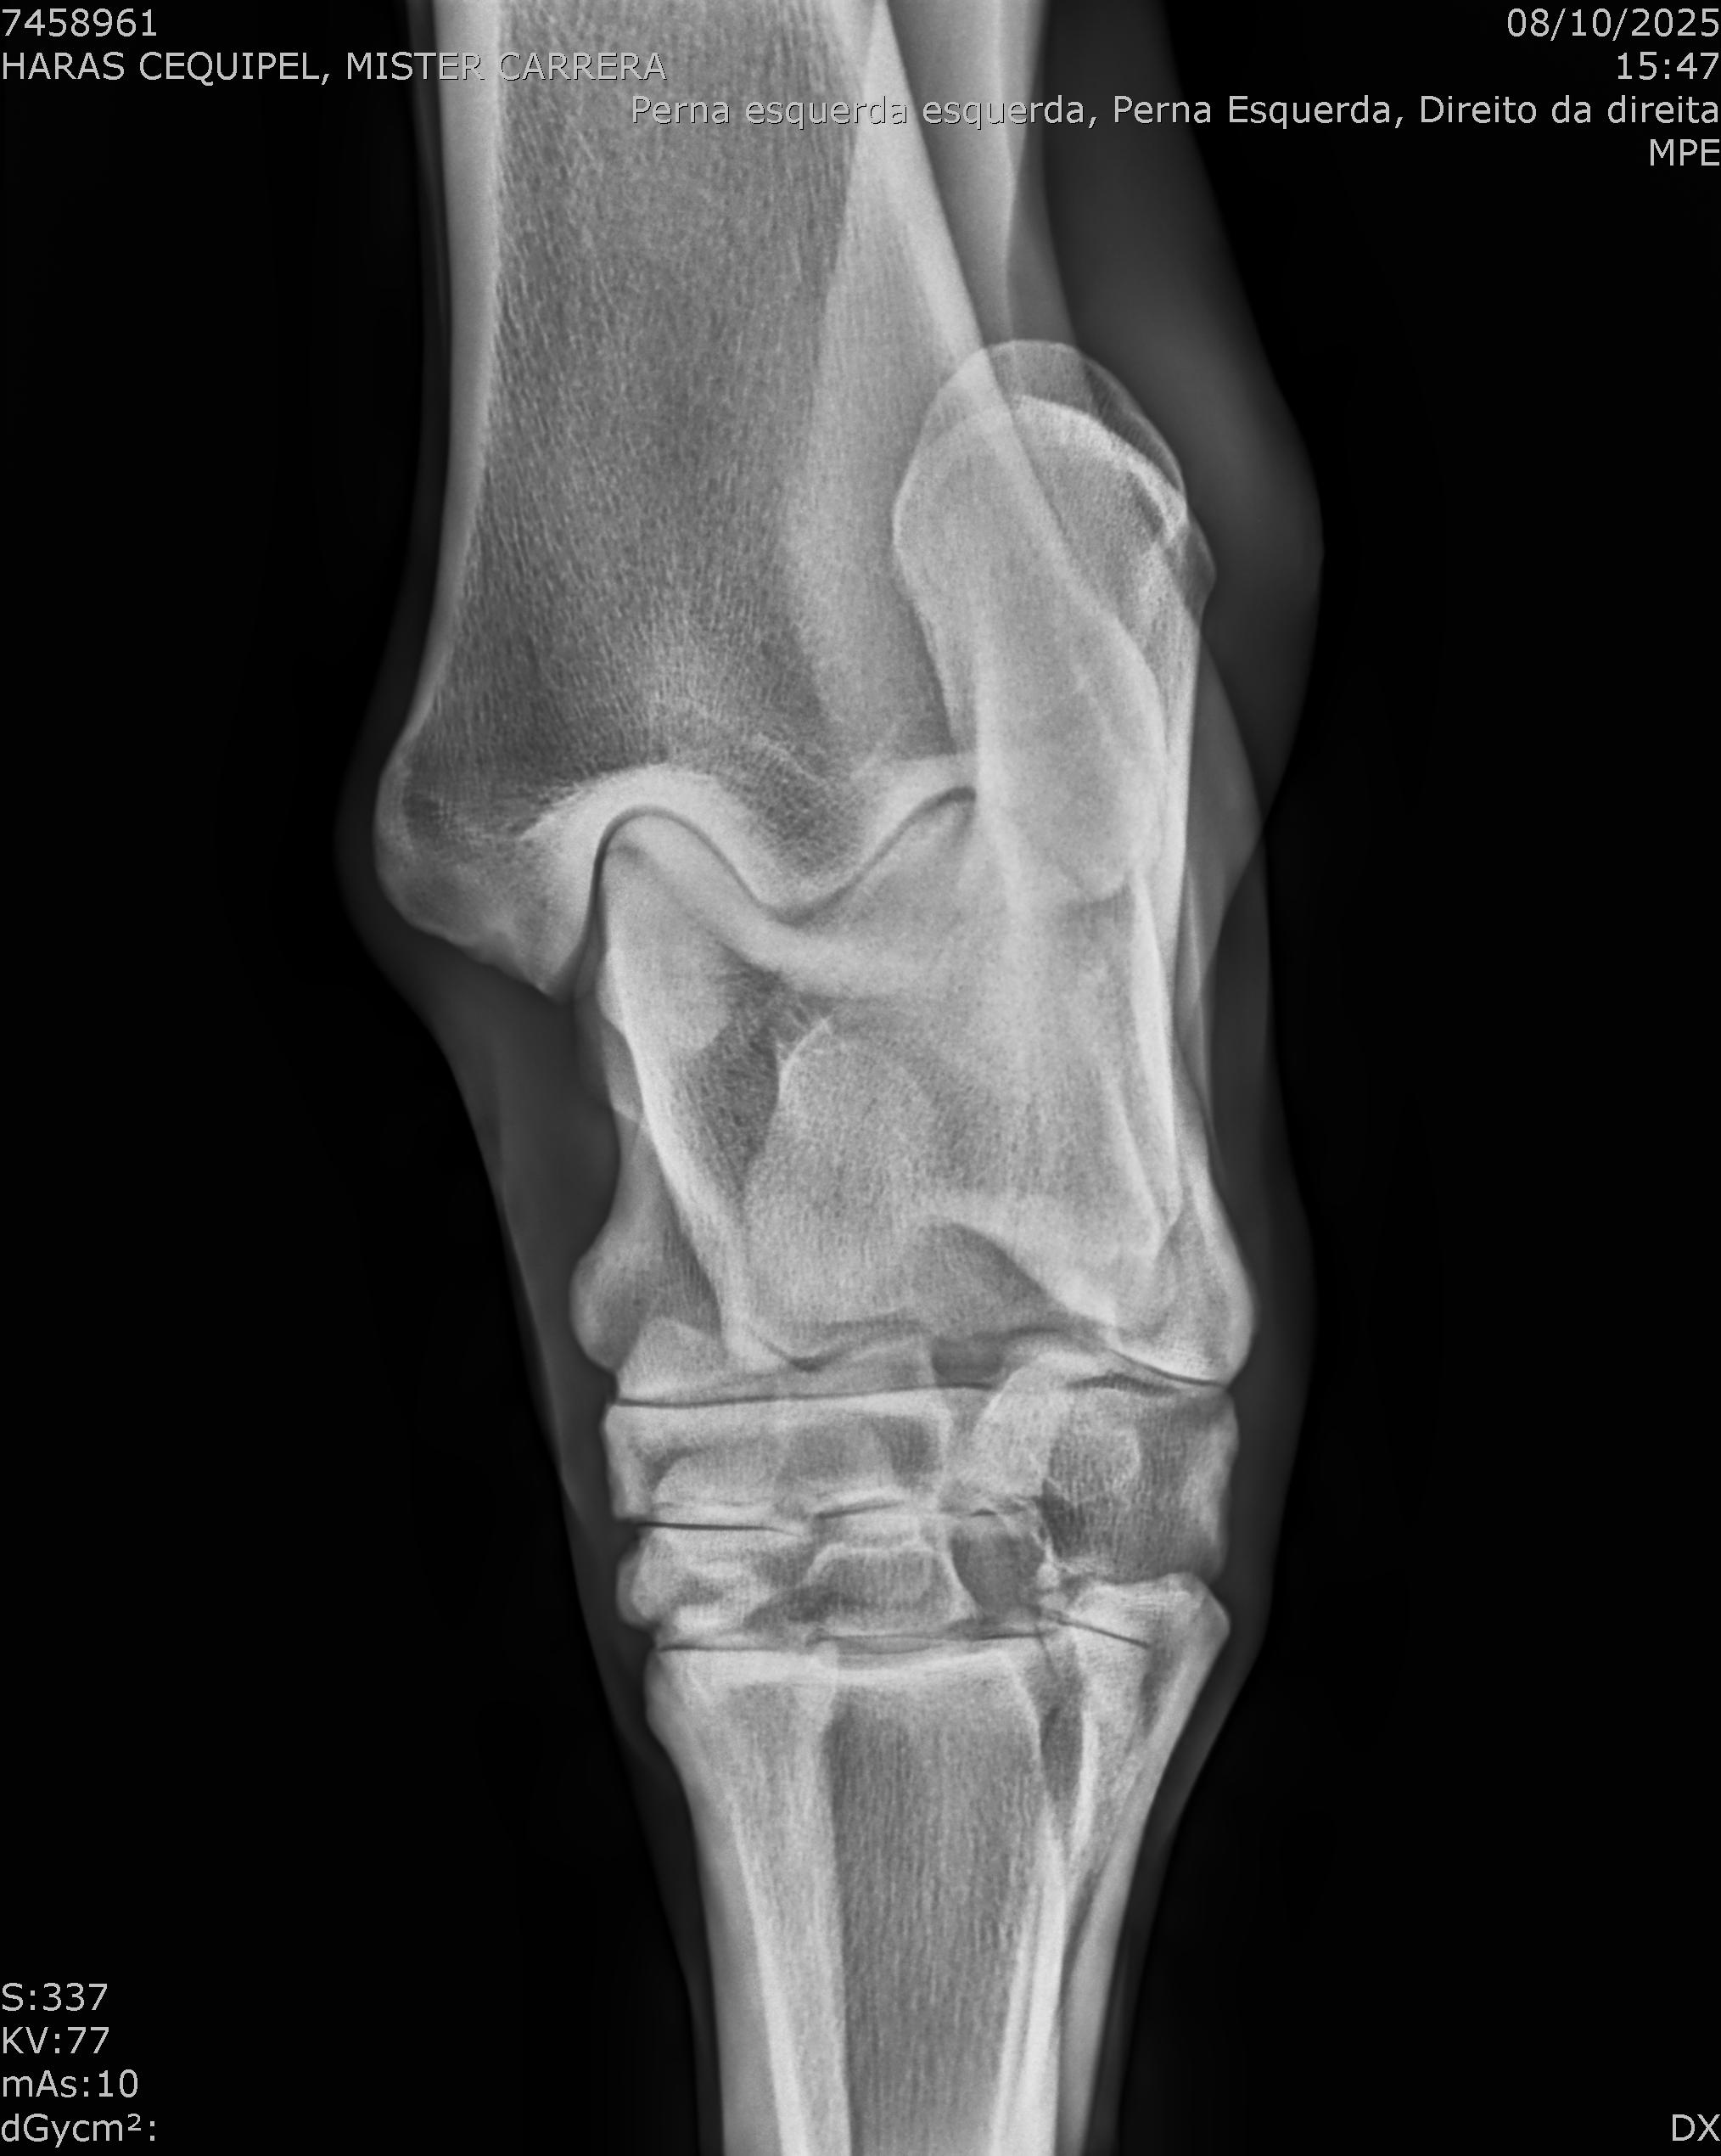

:: RAIOS-X DO LOTE